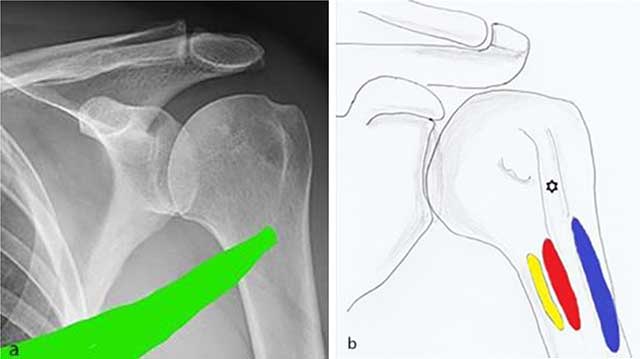

Figure 6

a) Spiral anatomical course of the teres major which may explain shearing forces leading to the periosteal stripping is demonstrated. b) Anatomical drawing showing the close anatomical relationship of the insertion of the teres major (yellow), latissimus dorsi (red) and pectoralis major (blue) tendon.